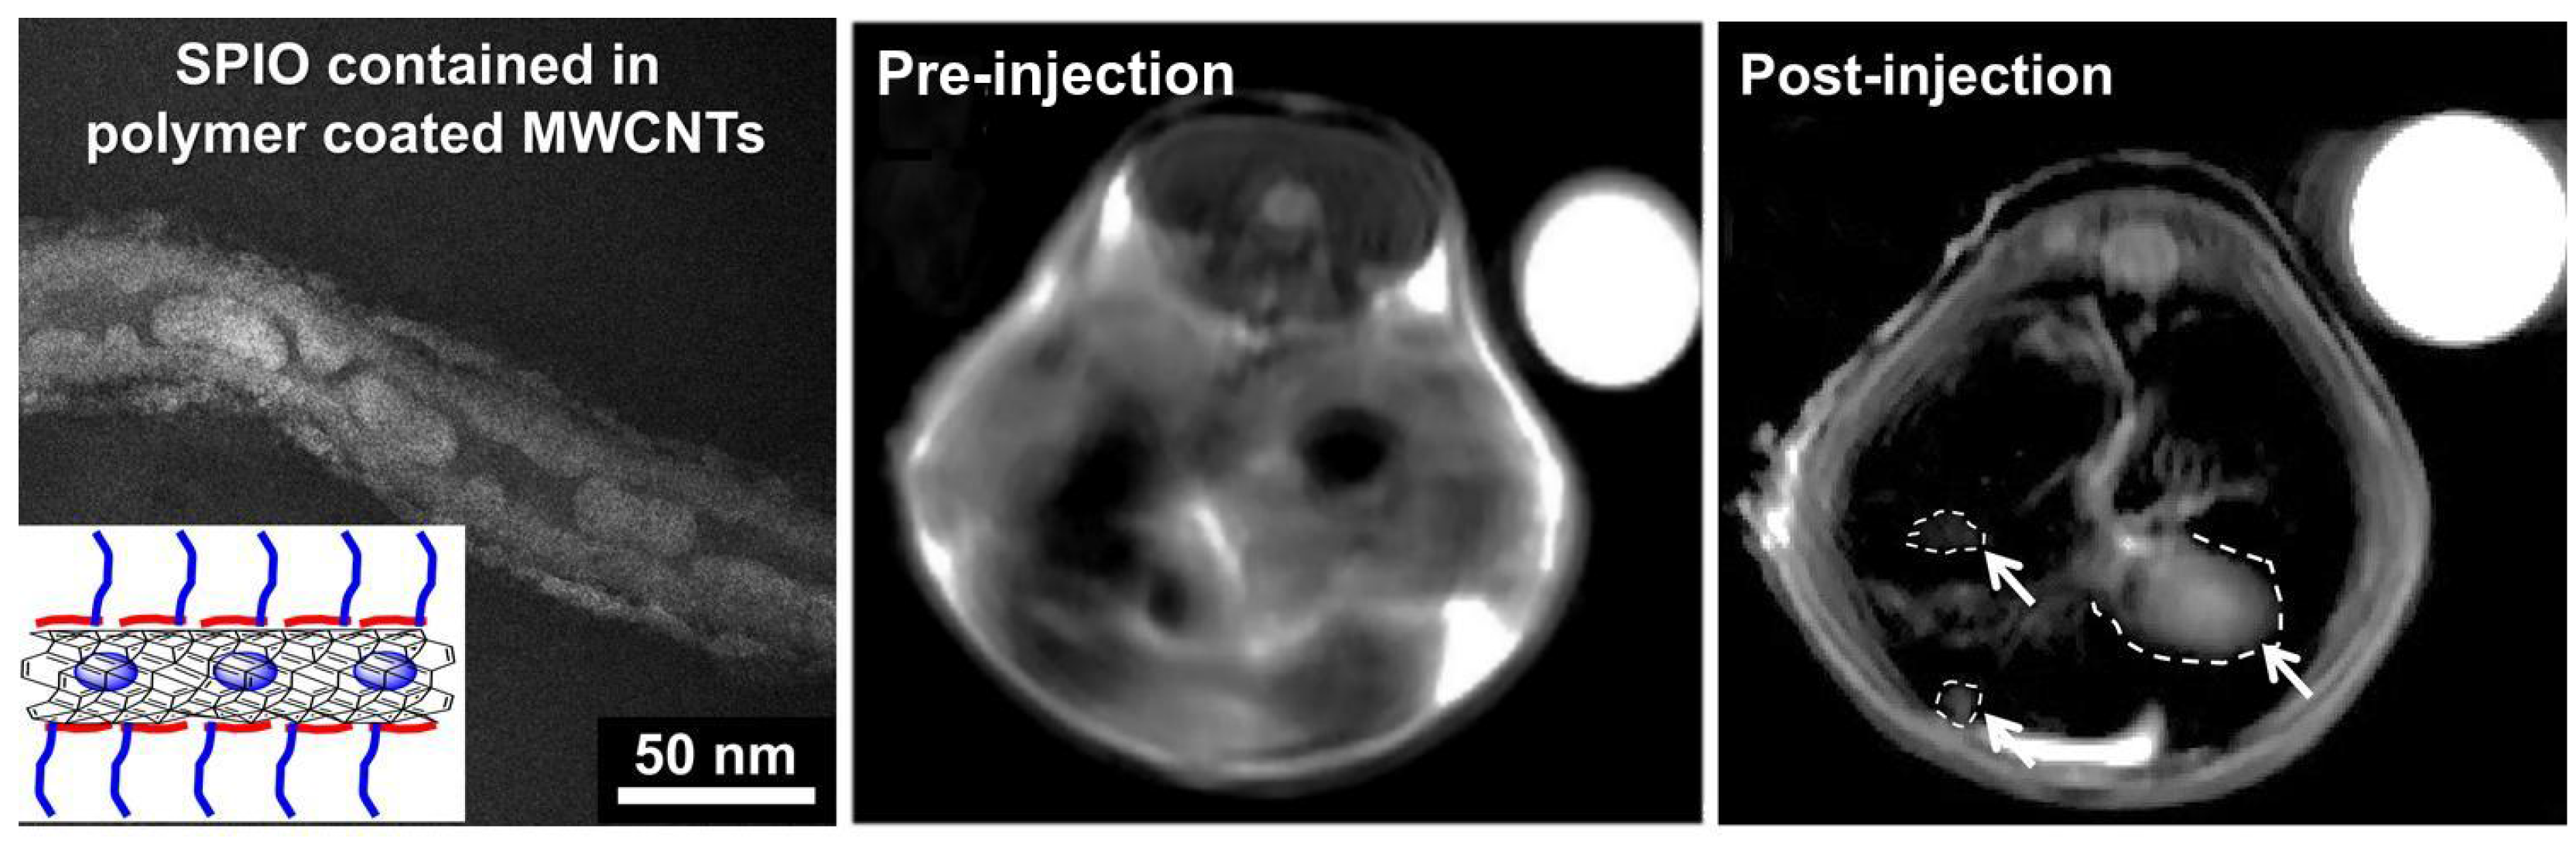

Magnetic Resonance Imaging (MRI) is currently one of the most powerful diagnosis tools in medical science [74]. MRI not uses ionizing radiation, but a high-intensity magnetic field to align the nuclear magnetization of hydrogen atoms in water within the body, taking advantage of the difference in water concentration among tissues to produce high-quality anatomical images with high spatial resolution [75]. MRI contrast agents are classified into two classes: spin-lattice relaxation agents, with larger effects on T1 shortening and spin-spin relaxation agents with larger effects on T2 shortening, where T1 and T2 are the proton relaxation times. In order to produce an MRI-active CNT CA, a paramagnetic or superparamagnetic agent must be conjugated to or encapsulated within the CNT platform [76,77]; moreover, a proper agent is needed to target tumors [78,79,80]. Recently, Liu et al. placed, inside the inner cavity of MWCN SuperParamagnetic Iron Oxide (SPIO), nanoparticles to create a T2-weighted contrast agent. To inhibit aggregation and improve their vascular biocompatibility, the SPIO-MWCNT were covered with a polymer (Figure 7, left). Diblock copolymers (PMETAC-b-PEGMA) were prepared by RAFT polymerization following the procedure described in [81]. The final polymer was composed of two units with very specific duties: the cationic PMETAC block was designed to electrostatically bind to the negatively-charged oxidized CNTs, while the second functional PEGMA block was designed to improve the aqueous dispersion stability of the hybrid material.

Figure 7.

On the left: TEM image of polymer-covered SPIO-MWCNT. In vivo MRI images of mouse liver pre- and post-injection of SPIO-MWCNT (white arrows indicate tumors) compared to the internal standard (water, top right). Adapted with permission from [82]. Copyright 2005 American Chemical Society.

Figure 7 (middle and right) shows in vivo MRI measurements’ image pre- and post-injection. A 55% increase in tumor to liver contrast ratio was observed comparing the two images, thus enhancing the detection of the tumor [82]. One of the most studied and used CA for the T1 shortening is the Gd ion [83,84,85], also in combination with CNTs [86,87]. To exploits such ions, Jahanbakhsh et al. modified the so-called gadonanotubes (i.e., gadolinium-linked carbon nanotubes) with diamine-terminated oligomeric poly(ethylene glycol) via a thermal reaction method in order to improve their water solubility and biocompatibility. The created complex increased the tumor targeting by means of a better EPR effect of tumor blood vessels [88]. Another effective way to exploit Gd ions is the one used by Marangon’s group. They functionalized MWCNT with a molecule called diethylenetriaminepentaacetic dianhydride (DTPA); such a molecule is said to be a chelating molecule; in other words, it has the ability to strongly bond (to chelate) another molecule or ion (Gd in this case) to itself. Bonding between MWCNT and DTPA was covalent, while the one between DTPA and Gd, despite the fact that it was not a covalent one, was still very strong, resulting (Figure 8) in a very stable compound with no risk of Gd release over time.